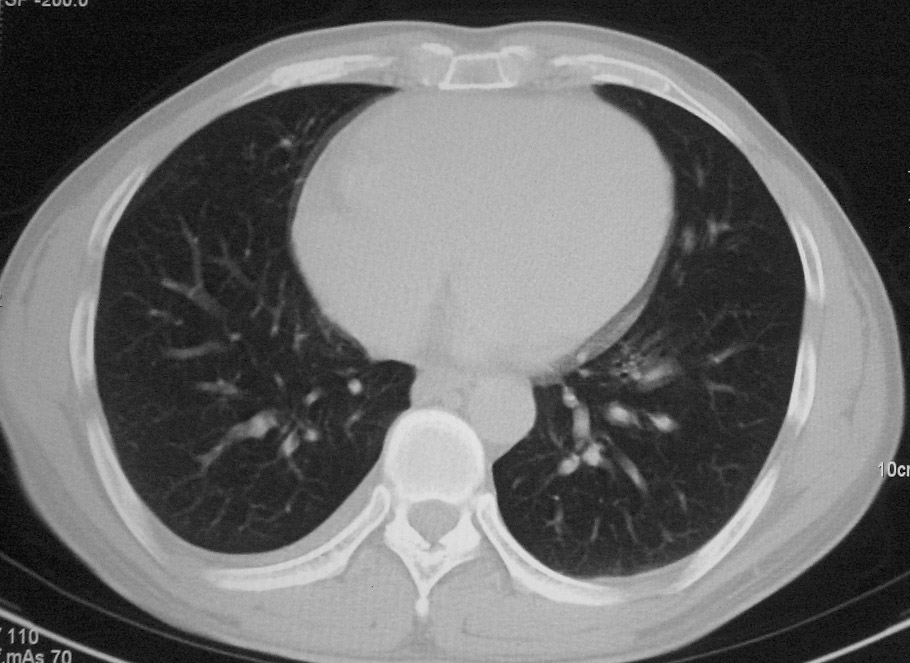

标题: CT5485:[原创]肺部占位请讨论

右上肺ca并肺不张,纵隔淋巴结转移

右肺上叶中央型肺癌并上叶肺不张、纵隔淋巴结肿大

右上叶支气管后壁明显增厚,支持右肺上叶中央型肺癌伴右上叶肺不张、纵隔淋巴结肿大。

考虑右上肺癌并肺不张,纵隔淋巴结转移

右上叶支气管后壁明显增厚,支持右肺上叶中央型肺癌伴右上叶肺不张、纵隔淋巴结肿大。建议支气管镜检查。

右上叶支气管开口变窄,纵隔见肿大的淋巴结。支持右上叶中心型肺癌并右上叶不张纵隔淋巴结肿大。

右肺上叶支气管后壁增厚,呈鼠尾状狭窄,纵隔内未见明显增大的淋巴结影,考虑为中央型肺癌伴右上肺不张